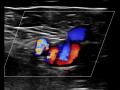

Doppler de membros inferiores - Cabeça do Mickey